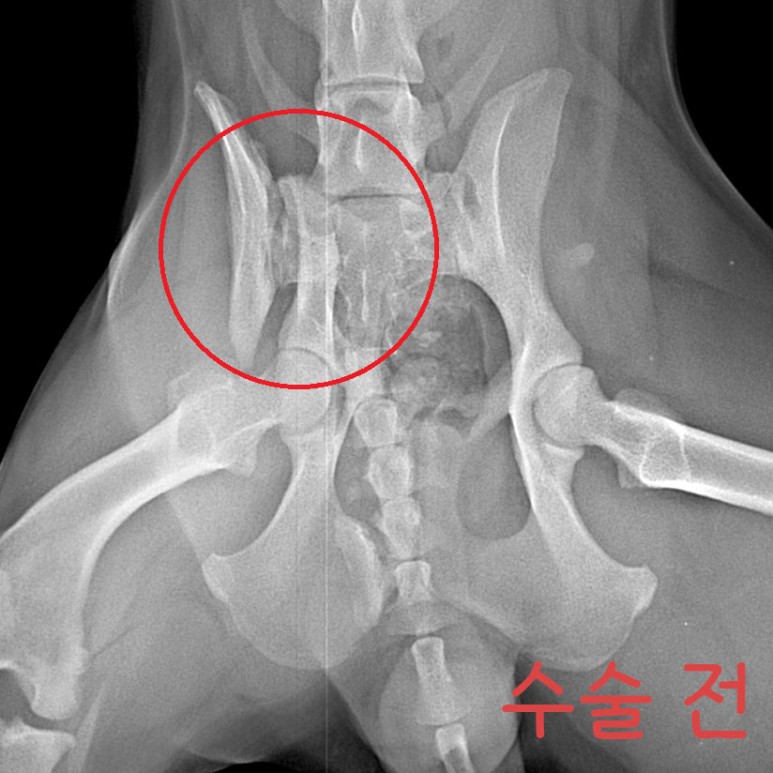

Çüµé! ¿À´ÃÀº '¸Û¼øÀÌ'¶ó´Â °¾ÆÁö¸¦ ¼Ò°³ÇÏ·Á°í ÇØ~! ¸Û¼øÀÌ´Â °³³óÀå ¶áÀå¿¡¼ Å»ÃâÇÑ ¾ÆÀ̾ß. ±ØÀûÀ¸·Î Å»Ãâ ÈÄ ÀÎõ °è¾ç±¸ ÁÖÀ§¸¦ µ¹¾Æ´Ù´Ï´Ù°¡ ±³Åë»ç°í¸¦ ´çÇß´Ù°í ÇÏ´õ¶ó±¸. £¨±×¶§±îÁö ½ÃÀå »óÀÎ ºÐµé¿¡°Ô ¸ÔÀ» °É ¾ò¾î¸ÔÀ¸¸é¼ Áö³Â´Ù°í ÇØ¤Ì¤Ì£© ÀÌÈÄ À¯±â°ß ¼¾ÅÍ¿¡ ÀÔ¼Ò ÈÄ, Áö³ 4¿ù 8ÀÏ ±¸Á¶µÇ¾ú¾î. ±×¸®°í Áö³ 4¿ù 17ÀÏ º´¿ø¿¡ ³»¿øÇØÁÖ¼ÌÂî! ³»¿ø ´ç½Ã ¾ÆÀÌÀÇ »óÅ´ ÀÌ·¯Çß¾î. - ¿ìÃø °ñ¹Ý»ÀÀÇ Àå°ñ³¯°³£¨iliac wing£© °ñÀý - °ñÀýµÈ Áö 1´Þ ÀÌ»ó µÇ¾úÀ¸¸ç, - À§ »çÁø¿¡¼ º¸½Ã´Â °Íó·³, ÃÊ·Ï»öÀ¸·Î Ç¥½ÃÇÑ 1¹øÀÌ È»ìÇ¥ ³¡ºÎºÐ¿¡ ¿¬°áµÇ¾î ÀÖ¾î¾ß ÇØ. - ÇÏÁö¸¸ °ñÀýµÈ Áö ¿À·¡µÇ¾î, ¾ûµ¢ÀÌ ±ÙÀ°ÀÇ À§Ãࣨadaptive shorteningÀÌ ¿¹»óµÇ¾ú¾î£© - ºÎ·¯Áø °ñ¹Ý»À°¡ ±²ÀåÈ÷ °ñ¹Ý ¾ÈÂÊÀ¸·Î µé¾î°¡ ÀÖ°í, - ±ÙÀ°ÀÌ Âª¾ÆÁ® ºÎ·¯Áø »À°¡ ¸Ó¸® ¹æÇâÀ¸·Î ¿Ã¶ó¿Í ÀÖ¾úÁö. µû¶ó¼ ¼ö¼úÀº ÀÌ·¸°Ô ÁøÇàµÇ¾ú¾î. - µÞ´Ù¸® ±ÙÀ° ¹× ¾ûµ¢ÀÌ ±ÙÀ°À» ÀÚ¸£°í Á¥Çô°¡¸ç °ñÀýµÈ ºÎÀ§¿¡ Á¢±ÙÇß°í, - ³»ÃøÀ¸·Î º¯À§µÈ Àå°ñ ³¯°³¸¦ ¹Ù±ùÀ¸·Î ²¨³½ ÈÄ ¿ø·¡ À§Ä¡¿¡ ¸ÂÃçÁÖ¾ú¾î. - °ñÀýµÈ Áö ¿À·¡µÇ¾î, ºÎ·¯Áø »À¿¡ ºÙÀº ±ÙÀ°ÀÌ ½ÉÇÏ°Ô º¯ÇüµÇ¾î ÀÖ¾ú¾î. - µû¶ó¼ ºÎ·¯Áø »À¸¦ ¿ø·¡ À§Ä¡¿¡ ¸ÂÃß´Â µ¥¸¸ 2½Ã°£ ÀÌ»óÀÌ ¼Ò¿äµÇ¾ú¾î. ¼ö¼úÀº ¸Å¿ì Àß µÇ¾úÀ¸¸ç, - ¼ö¼ú ÈÄ¿¡´Â 1ÁÖÀϰ£ ÀÔ¿øÀå »ýȰÀ» Çß¾î. - Åð¿ø ÈÄ 4ÁÖ°£Àº ½Ç³» ÀÚÀ¯ »ýȰÀ» Çϸç, - 2~4ÁÖ¿¡ ÇÑ ¹ø¾¿ X-ray ÃÔ¿µÇÒ ¿¹Á¤À̾ß. - ¿À¸¥ÂÊ ´Ù¸®ÀÇ ¿îµ¿¼º ¹× ¹èº¯Àº Á¤»óÀûÀ¸·Î ÇÏ´ÂÁö ¸ð´ÏÅ͸µÇÒ ¿¹Á¤À̰í! - ±×¸®°í Ç÷¹ÀÌÆ®ÀÇ ±æÀ̰¡ Á¶±Ý ±ä µíÇÏ¿©, 6°³¿ù µÚ Ç÷¹ÀÌÆ® Á¦°ÅÇÒ ¿¹Á¤ÀÌÁö! ±×¸®°í ÀÌ°Ç Åð¿ø Àü ÂïÀº »çÁø! ³Ñ Àß µóÁö!! ¿ì¸® ¸Û¼øÀÌ ³Ñ³Ñ ±âÆ¯ÇØ! ¤Ð¤Ð¤Ð ¸Û¼øÀÌ´Â »ç¶÷¿¡ ´ëÇÑ »óó°¡ ÀÖÀ» ÅÙµ¥µµ, ³Ê¹« ÂøÇØ¼ ´õ´õ¿í ¸¶À½ÀÌ ¾ÆÆÍ¾î ¤Ì¤Ì... Ä¡·á ÈÄ¿¡´Â ±¸Á¶ÀÚ´Ô ´ì¿¡¼ Áö³»¸é¼, ÀÔ¾ç º¸³¾ ¿¹Á¤À̶ó°í ÇØ! ¿ô´Â ¸ð½Àµµ ¿¹»Ú°í ÂøÇØ¼ ²À ÁÁÀº °¡Á·À» ¸¸³¯ °Å¾ß ¸Û¼ø¾Æ! ¸Û¼øÀÌ ³Ê¹«³Ê¹« »ç¶ûÇØ! ³Ê¹«³Ê¹« ±âƯÇϰí ÂøÇÑ ¸Û¼øÀÌ °í¸¶¿ö ¢½ ¢½ °¡Á·ÀÇ Ç°ÀÌ Àý½ÇÇÑ ¸Û¼øÀÌ¿¡°Ô ¸¹Àº °ü½É ºÎÅ¹ÇØ!!! À̸§: ¸Û¼ø £¨¿©¾Æ, Áß¼ºÈ ¿Ï·á£© ³ªÀÌ: 1¼¼ Ư±â: ÇØ¸¼Àº ¿ôÀ½¢¾